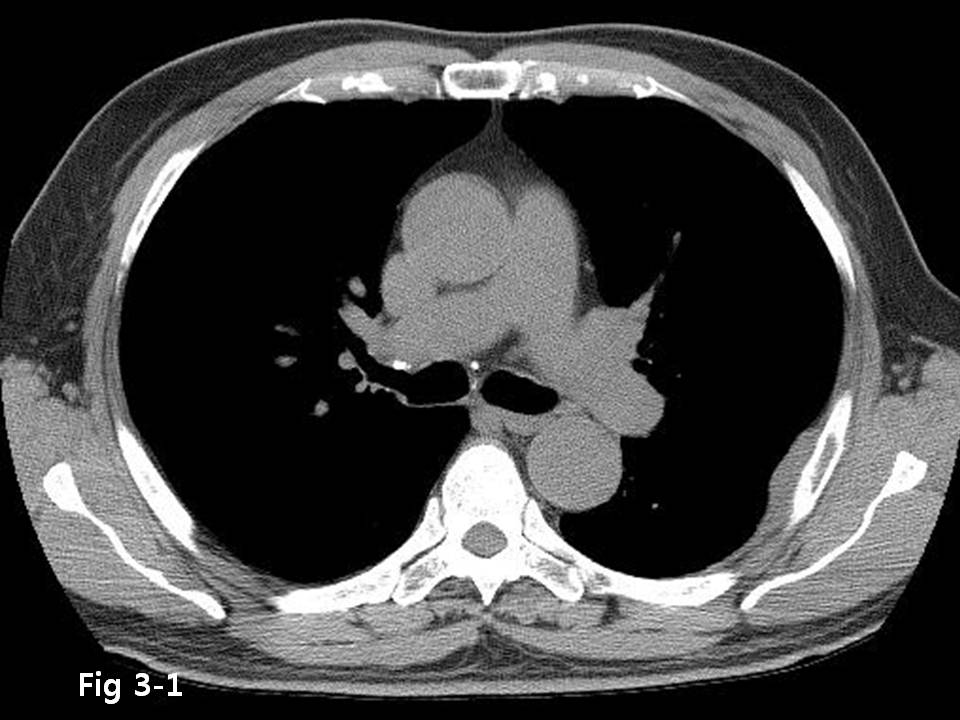

M/70

Chest pain  È£¼Ò

Chest CT ¿Ã·Á ÁÖ¼¼¿ä